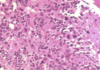

What is this slide showing?

Purkinje fibres (with PAS proceedure - magenta)

- Large modified muscles

- Large vacuoles

- Few myofibrils therefore pale H and E

- Stores of glyocogen (PAS)

Cardiac conduction